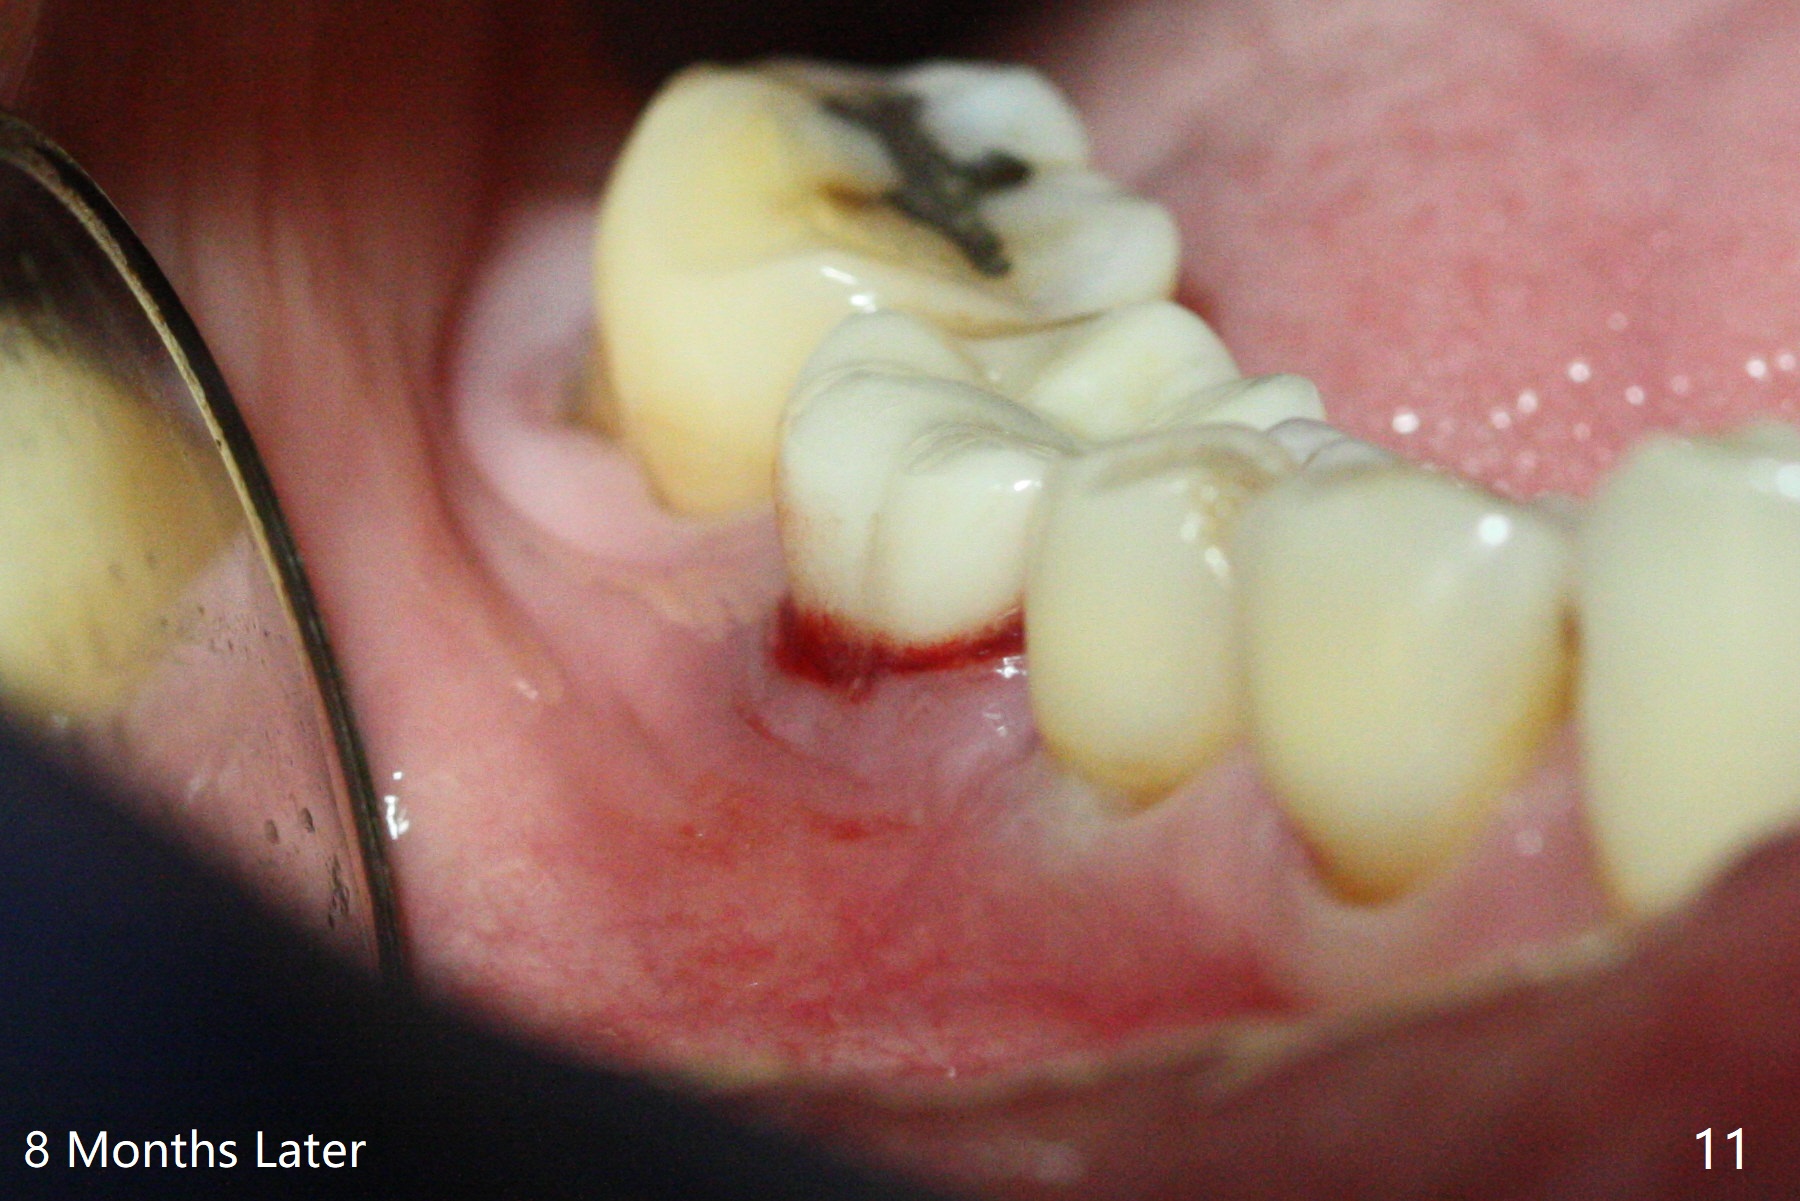

There is no symptom or sign of periimplantitis 3 years 8 months post 2nd bone graft (Fig.7-10). However, the patient complains of gingival hemorrhage 8 months later (Fig.11,12 (buccal), 13 (lingual view)). Water Pik is recommended.